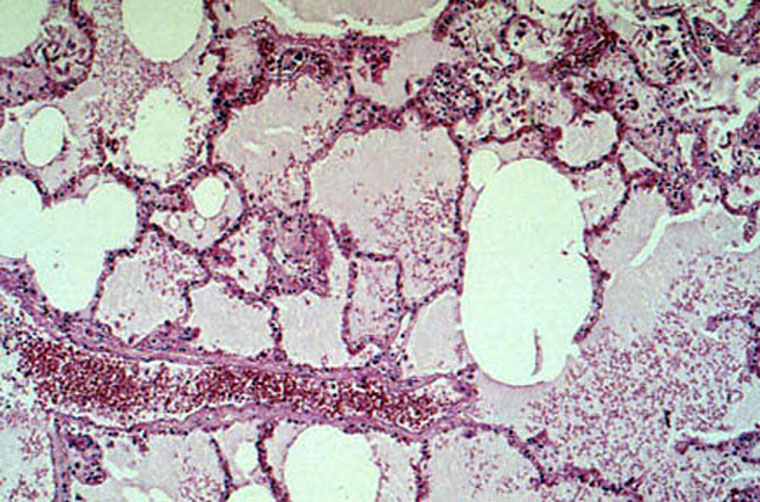

Chronic Passive Congestion of the Lung/Histology/40  Dr Ralph Leischner